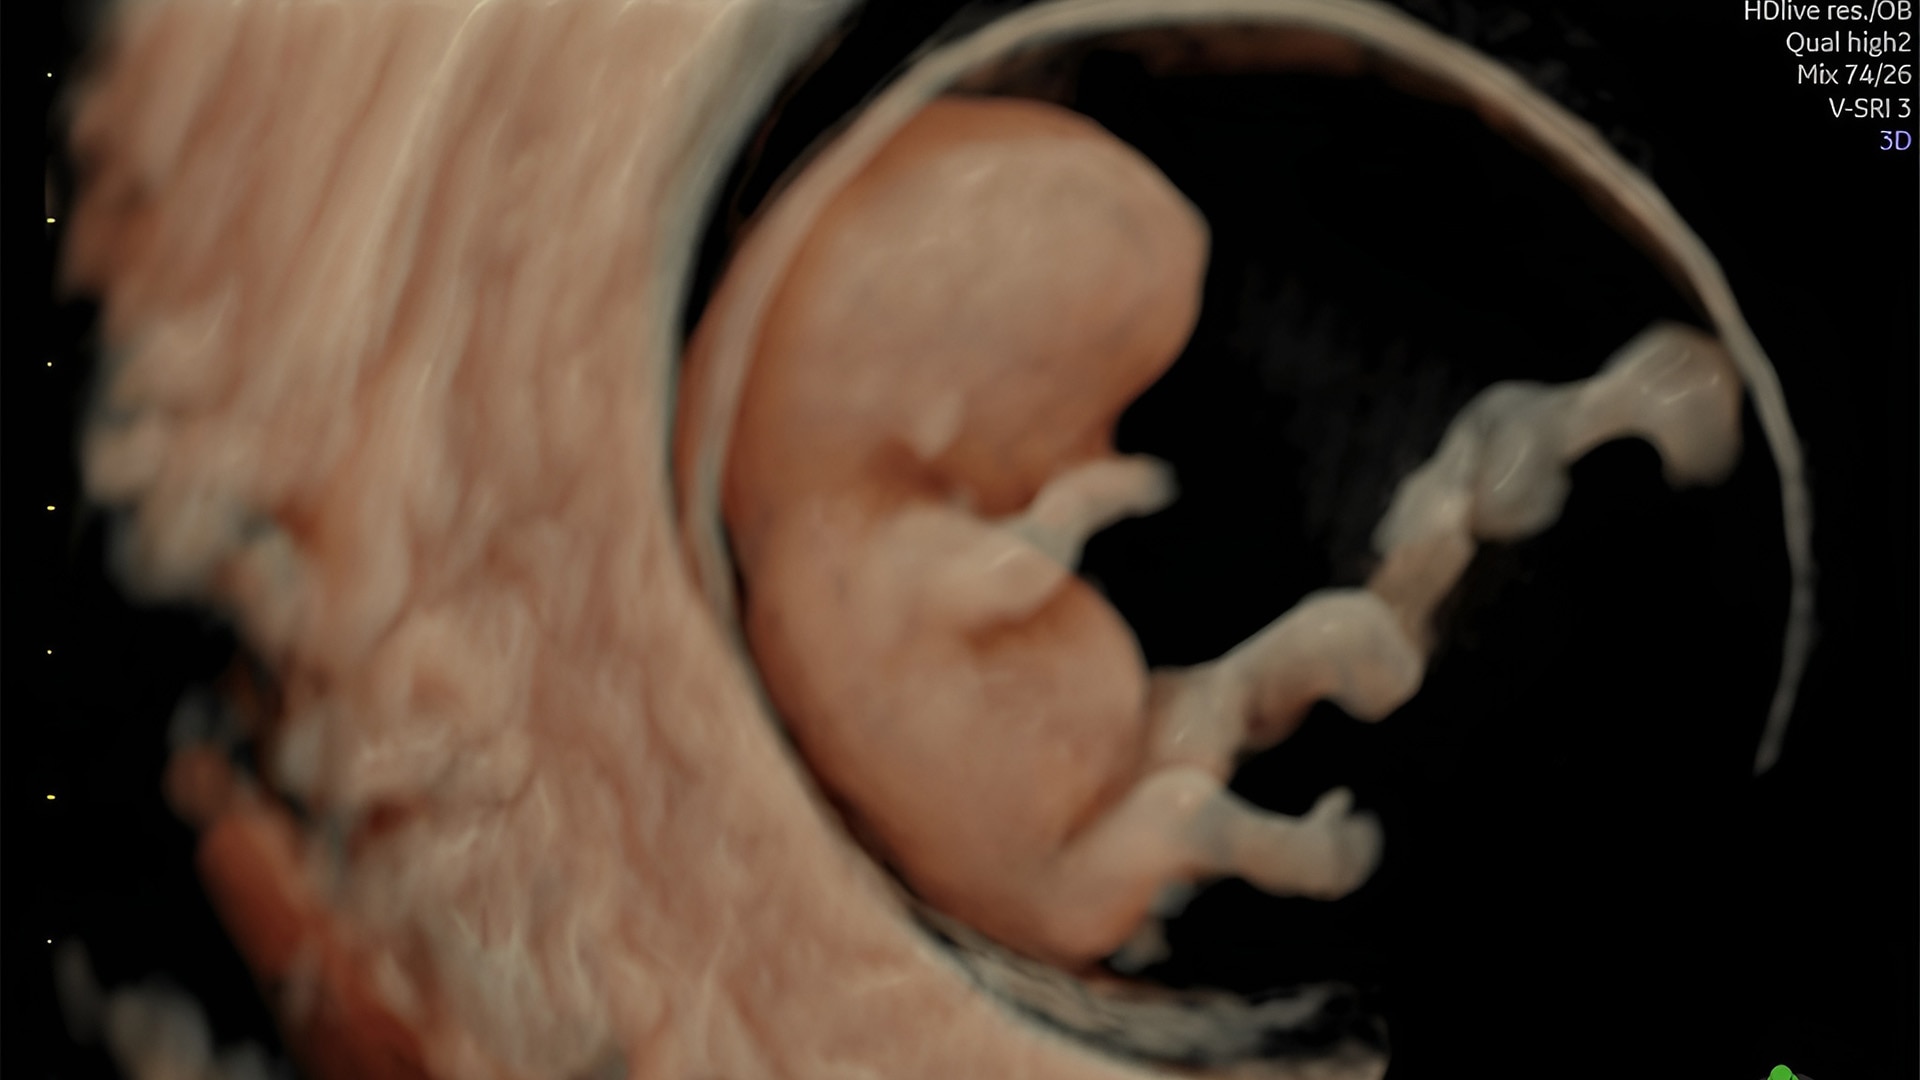

First trimester exams

Perform detailed exams with high-resolution for early insights to fetal health